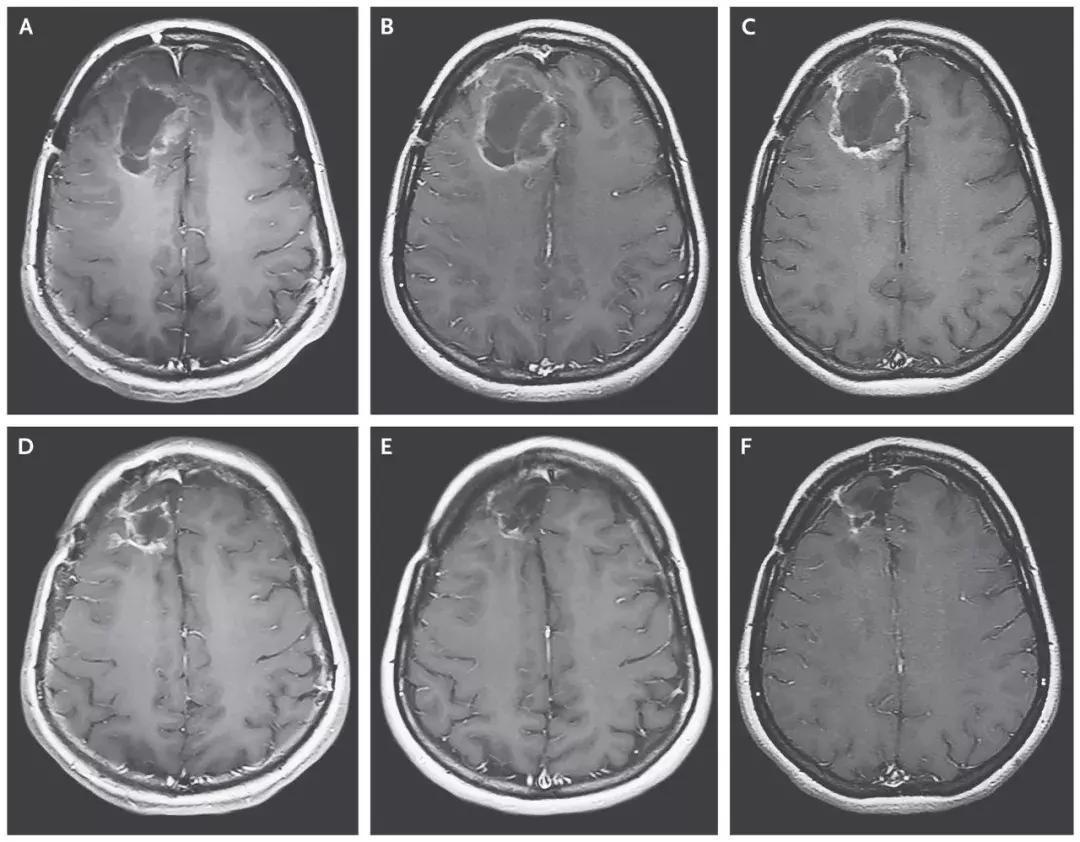

试验结果

- 治疗组的中位生存期是12.5个月,与11.3个月的历史数据相差无几;

- 在2年这个时间节点上,治疗组的生存率是21%,已经比历史数据(14%)高出50%;

- 在3年这个节点,治疗组的生存率同样为21%,而历史数据仅为4%。这意味,经过病毒的治疗后,这个生存率猛增5倍!

溶瘤病毒创造恶性脑瘤完全缓解的治疗奇迹!

截止2018年3月20日,8名患者对治疗产生治疗应答,2名患者的脑胶质瘤病灶完全消失,达到了完全缓解!

▲患者脑部肿瘤的缩小清晰可见(图片来源:《NEJM》)

这位患者,经过PVSRIPO溶瘤病毒治疗7个月后,病情复发后使用洛莫司汀治疗,经过12个月的洛莫司汀治疗后,病人的病灶完全消失并保持了20个月的无病状态,并且在PVSRIPO溶瘤病毒治疗发生出血后57.5个月仍然存活。